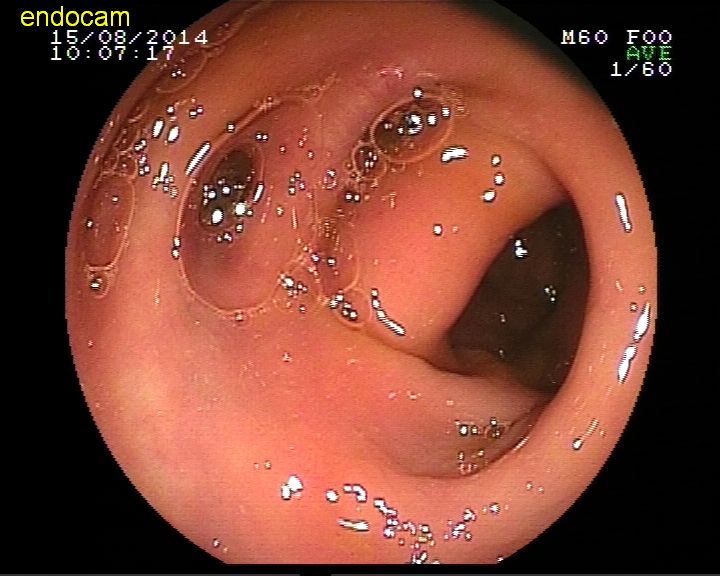

Kolonda divertikül